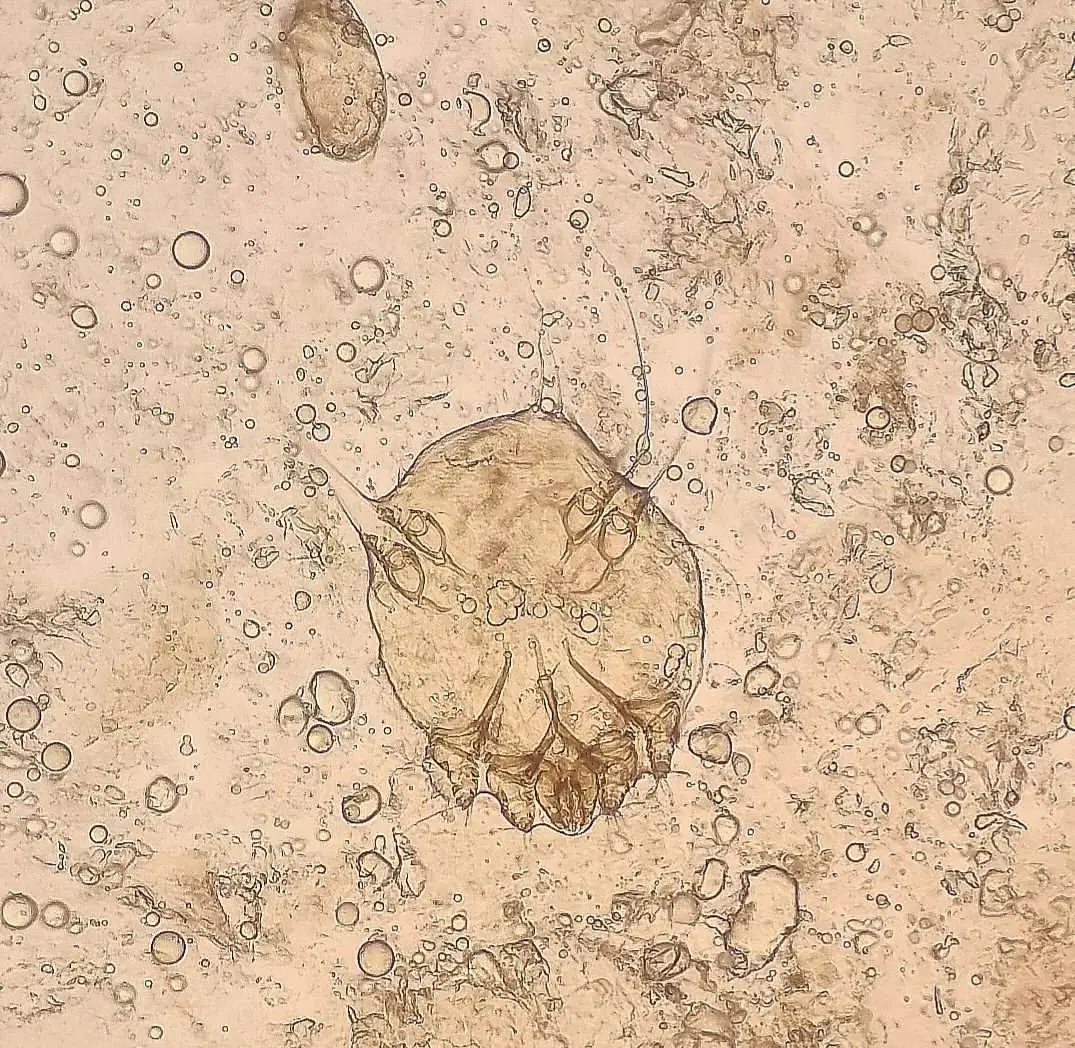

Sarcoptes scabiei, the human itch mite, causes scabies. You cannot see them with your naked eye, but under a microscope, you will notice that it has eight legs and a round body. The mites burrow just under the skin and make a tunnel where they reside, feed and poop.

Female mites lay eggs that hatch into larvae, which can travel to the skin surface. These mites can then spread to other areas of the skin or the skin of other people. Your skin reacts to these mites and their waste with intense itching and rashes. It can cause secondary infections due to scratching if left untreated.